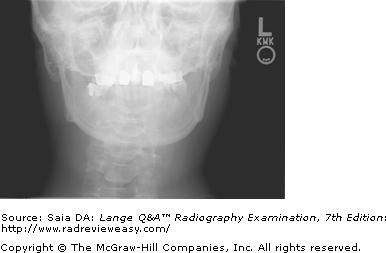

None of the above statements is correct. Analysis of the casr database. Basilar skull fractures, breaks in bones at the base of the skull, require more force to cause than cranial vault fractures.

Simply stated, a basilar skull fracture refers to any fracture found at the base of the skull. Purposes only, and are not intended for diagnosis of any illness. Such a type of fracture requires immediate medical attention. Partial acquisitions are difficult to manage from an acquirer's perspective, however they have been observed frequently. Answer the following questions and then press 'submit' to get your score. D) the average velocity is for the entire time interval and therefore cannot occur at the midpoint of the time interval alone. (c) cookies are very helpful in keeping track of users in developing online shopping cart applications, personalized portals and in advertising on web sites. The absence of raccoon eyes or battle's sign does not rule it out. It is usually a result from strong blunt force signs/symptoms of a basilar skull fracture: Where the fracture is one thin line with no additional lines splintering from it and no compression or distortion of the bones. Transcribed image text from this question. Which of the following figures correspond to possible values that pca may return for (the first eigen vector / first principal this is correct, as it maintains the structure of the data while maximally reducing its dimension. This type of fracture may be seen with or without a cut in the scalp. Graffiti is a serious problem in modern cities. A skull fracture is a break in a skull bone, and the primary cause is trauma to the head. Most likely has a concomitant basilar skull fracture. Basilar skull fractures are linear fractures that occur anywhere along the skull base from the cribriform plate to the occipital condyles.